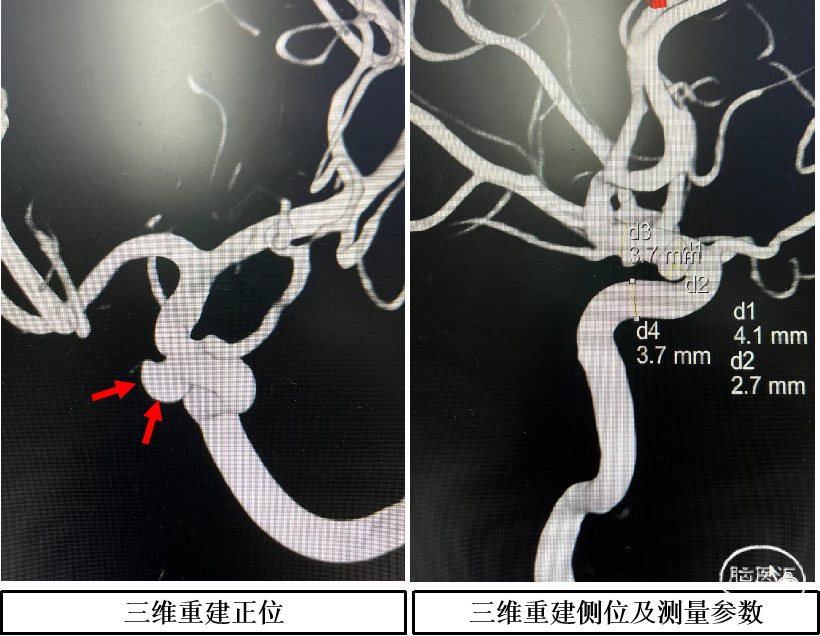

术前影像学检查结果

左侧眼段动脉瘤。

依据动脉瘤3D,调整机架位置使得动脉瘤及载瘤动脉显影最佳,Echelon-10微导管塑形理想,顺利超选至瘤内,先尝试单纯弹簧圈栓塞,必要时再采用支架辅助。